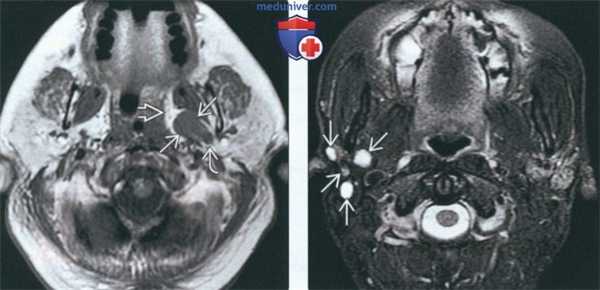

(Слева) На аксиальной МРТ (Т1ВИ) в глубокой доле левой околоушной железы визуализируется грушевидное объемное образование с промежуточным сигналом. Окологлоточный жир смещен кпереди и кнутри. Отсутствует жировая пластинка между опухолью и глубокой долей околоушной железы, что свидетельствует об истинной интрапаротидной ДСО.

(Справа) На аксиальной МРТ (Т2ВИ FS) определяются множественные мелкие образования в ложе удаленной правой околоушной железы. Рецидивирующая ДСО обычно множественная и напоминает виноградную гроздь.